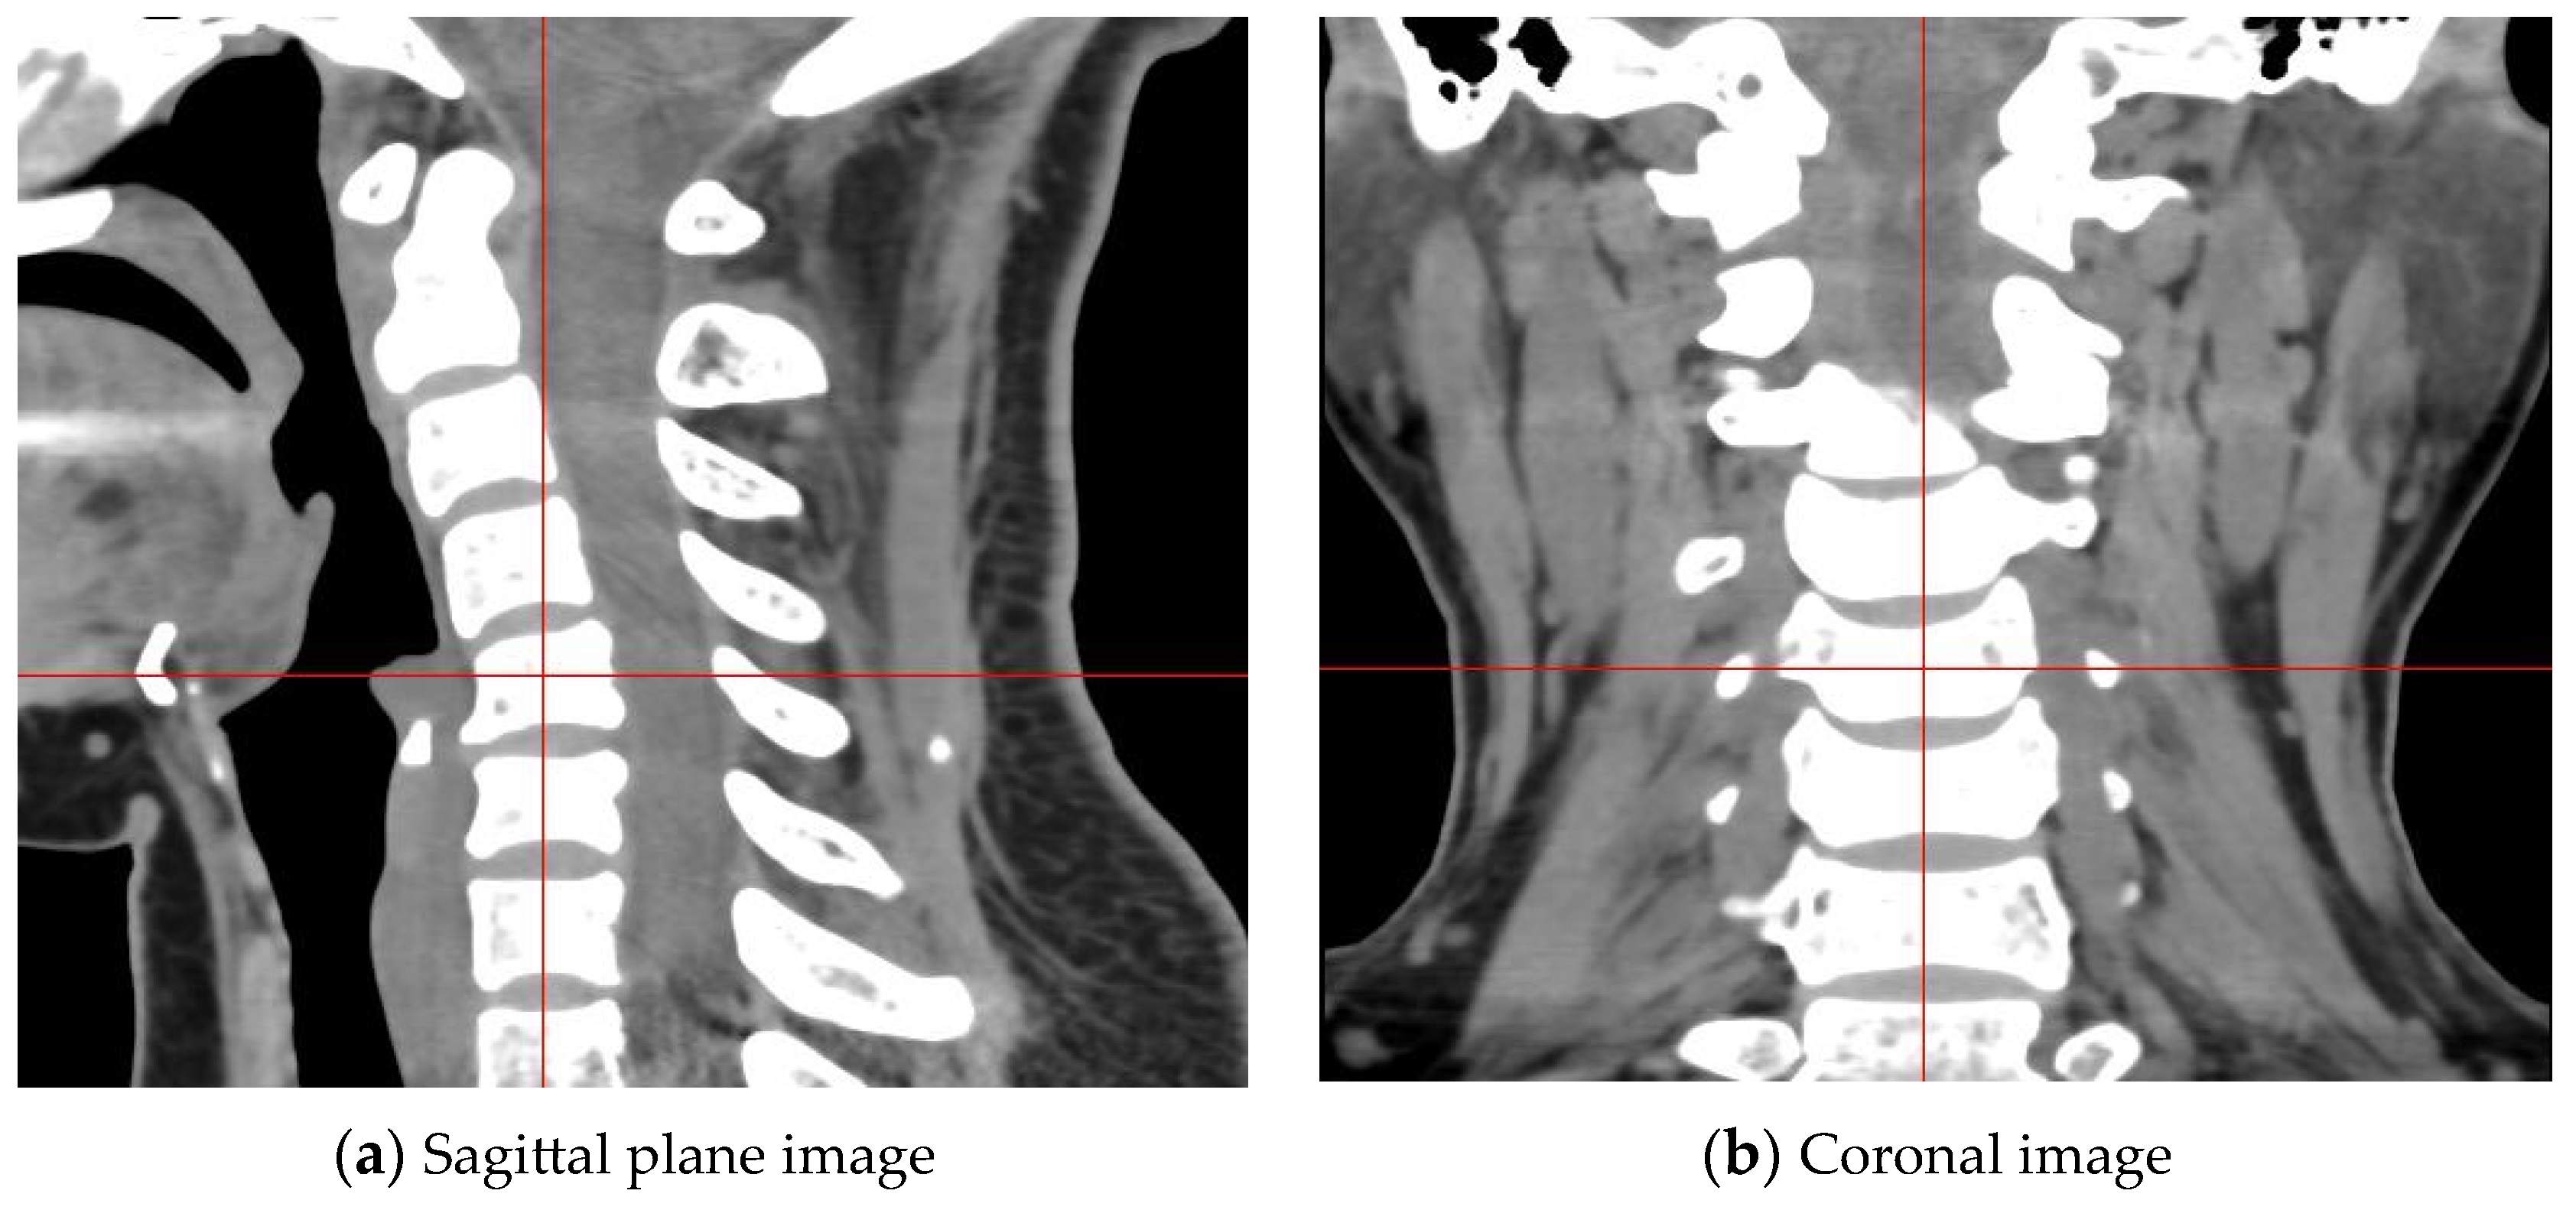

- Datasets specifically aimed at cervical intervertebral disc segmentation are developed. The proposed datasets incorporate inter-layer interpolation to address the inconsistency in longitudinal and transverse pixel spacing in CT sequence images. By selecting frames with prominent intervertebral disc regions through data significance selection and then constructing data groups where three consecutive layer images correspond to one label via manual annotation, the datasets provide important support for research in cervical disc segmentation.

3.5. Construction of Cervical Intervertebral Discs Segmentation Datasets